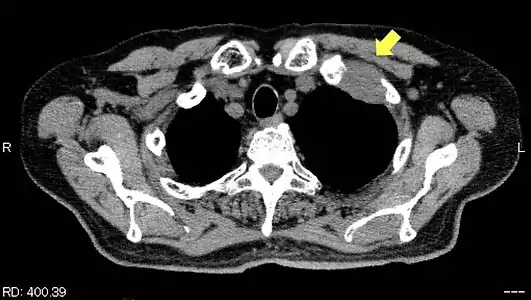

TDM d'une tumeur de Pancoast gauche envahissant l'arc antérieur de la 1re et de la 2e côte (flèche jaune). TDM d'une tumeur de Pancoast gauche envahissant l'arc antérieur de la 1re et de la 2e côte (flèche jaune).

Les côtes sont envahies de manière isolée chez 65 % des patients[15] ; seulement 8 % présentent un envahissement en bloc des côtes et des vertèbres adjacentes[15].